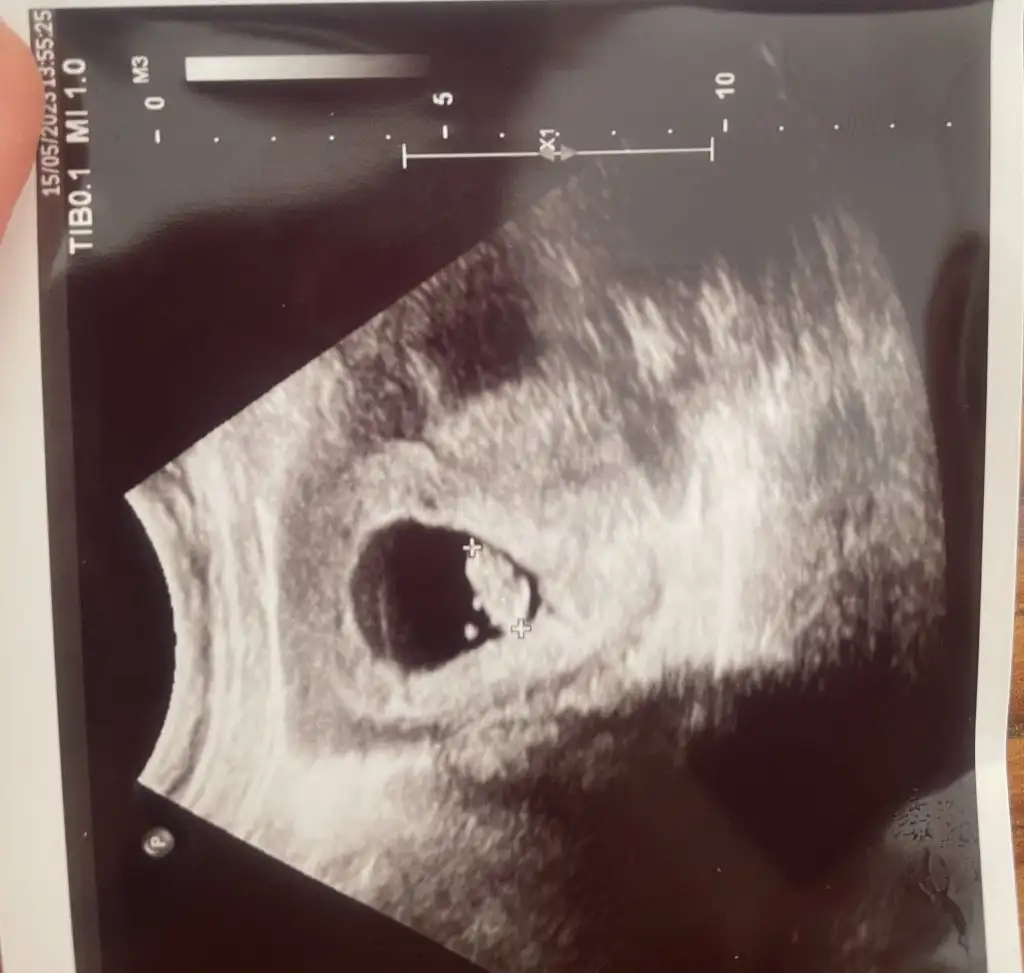

Ayy benimkine de bakar mısınKız bebege benziyor canım saglıkla gelsin inşallah

Tabiki canım at bakalımAyy benimkine de bakar mısın![]()

Teşekkür ederim inşallahBurda kıza benziyor canım saglıkla gelsin![]()

Burda kıza benziyor canım saglıkla gelsin![]()

Banada tahminde bulunabilrmisinizBurda kıza benziyor canım saglıkla gelsin![]()

Senşnkide kız canım saglıkla gelsin